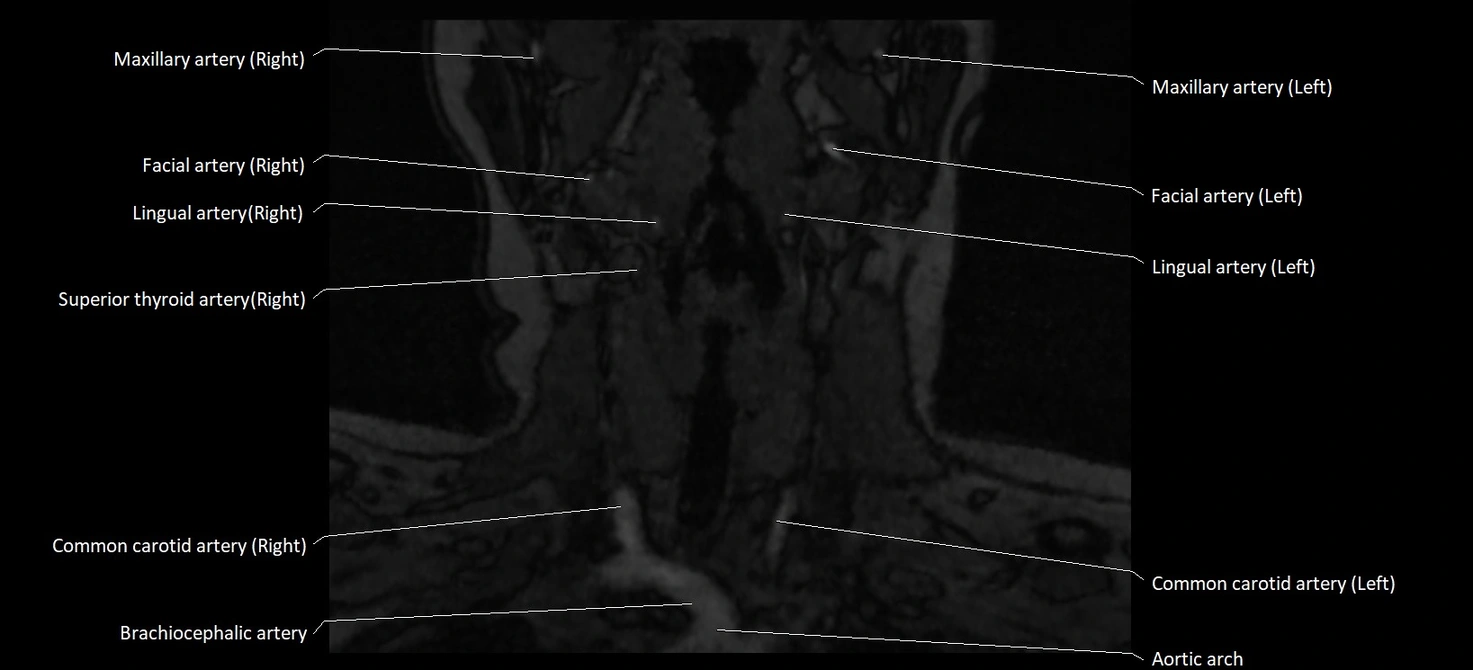

MRI images

image

CT image